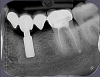

OMFS Опубликовано 19 июля, 2013 Поделиться Опубликовано 19 июля, 2013 История:имплантация в 2006 несколько дней назад поломался мост, появилась подвижность и после небольшая болезненность при накусывании.КТ 2012 г.прицельный снимок вчерашний.Достали сегодня. 4 Ссылка на комментарий